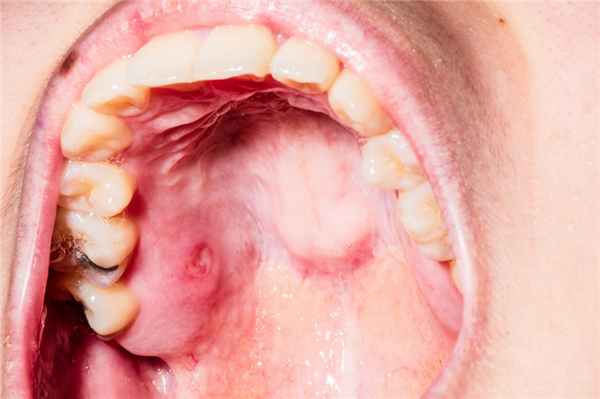

Слизистая полости рта краснеет и отекает, увеличиваются регионарные лимфоузлы. Через несколько дней на языке и внутренней поверхности щек возникает пузырьковая сыпь, а внутри высыпаний находится полупрозрачная жидкость. После вскрытия пузырьков появляются мелкие эрозии, которые покрыты желтоватой пленкой.

Кандидозный стоматит характеризуется образованием белого или желтоватого творожистого налета. Распознать травматический стоматит легче, поскольку ему предшествует повреждение или рядом находится источник травмы — сколотый зуб или шершавая пломба.

Проявления болезни зависит от вида и тяжести, но для всех воспалений характерны признаки следующего синдрома: покраснение слизистой в одном или нескольких местах: на щеках, под языком и на нем, на деснах. Затем область покраснения отекает, темнеет, покрывается белесым налетом. Появляется боль, которая усиливается во время еды и при питье. Довольно быстро пятнышко превращается в афту (язвочку), покрытую сероватым (фибринозным) налетом. Если его соскоблить, афта начинает кровоточить.

Кандидозный стоматит у взрослых и детей проявляется образованием белого налета на на небе, деснах, языке. При попытке его удалить, ткани начинают кровоточить. Обычные жалобы:

Афты всегда четко очерчены, не более 1 см в диаметре. Сначала появляется красное пятно круглой или овальной формы, потом оно начинает выступать над слизистой, покрывается сероватым налетом. Затем в основании образуется инфильтрат. Он заполняется некротическими массами. Через 3-4 дня афта вскрывается, гнойный секрет выходит наружу, оставляя красное пятно, которое быстро исчезает. Затем афта появляется на новом месте и все повторяется.

Симптоматика зависит от вида патологии, но есть общие клинические проявления. Как правило, болезнь начинается не остро. Слизистые становятся красными, в области очага поражения появляется припухлость, болезненность, чувство жжения. Как выглядит стоматит можно посмотреть на фото.

Если это бактериальная инфекция, то через день в месте заражения возникает язвочка и с красным ореолом, расходящимся от центра. Язва покрыта белым налетом. В этот период повышается слюноотделение, появляется неприятный запах. Боли беспокоят больного не только при употреблении пищи, но и в состоянии покоя.